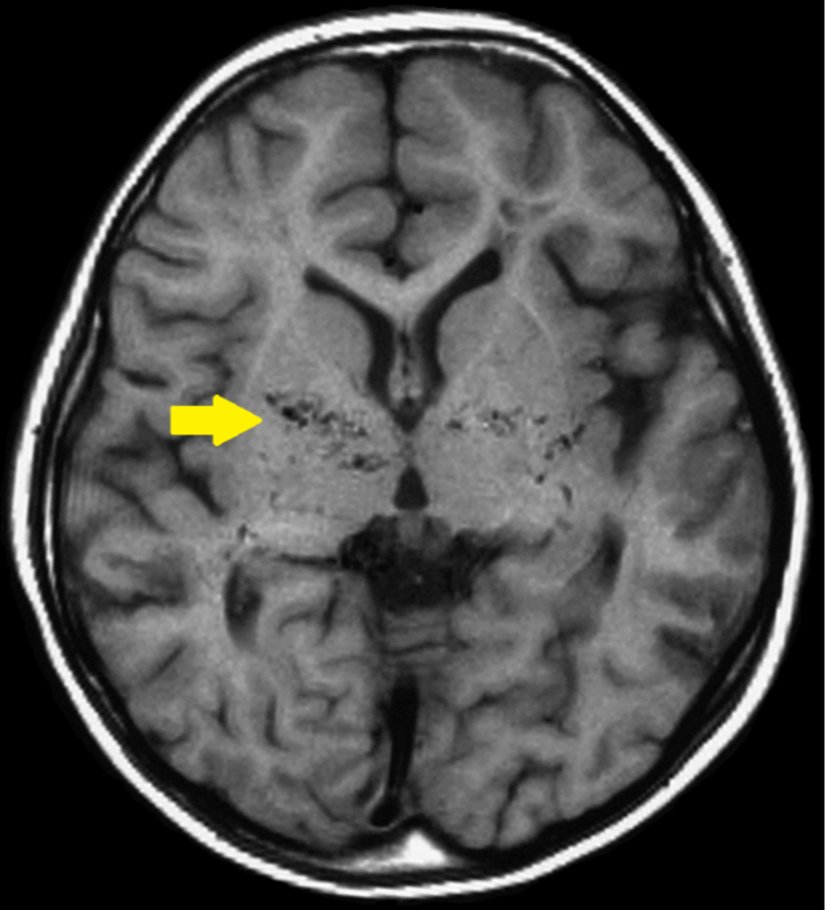

Manyetik Rezonans Anjiyografi (MRA), serebral anjiyografinin alternatifi olarak kullanılabilir. Bu yöntem, manyetik rezonans görüntüleme (MRG) prensiplerini kullanarak damarların görüntülerini oluşturur. Genellikle serebral anjiyografiye göre daha düşük risk içerir.[7]

Tanıda etkili olan bir diğer unsur, hastanın klinik belirtileri ve görüntüleme bulgularıdır. Moyamoya hastalığının belirgin bulguları genellikle supraclinoid iç karotis arterleri ve bunların proksimal dallarını içerir.[7]

Moyamoya hastalığının teşhisinde serebral anjiyografi genellikle en güvenilir yöntem olmakla birlikte, MRA gibi non-invaziv yöntemler de kullanılabilir. Teşhis sürecinde hastanın genel sağlık durumu, alerji öyküsü ve kontrast madde kullanımına karşı hassasiyet dikkate alınmalıdır. Teşhis, uzman bir sağlık profesyoneli tarafından detaylı bir değerlendirme sonucunda konmalıdır.[7]

Etimoloji

Japonca'da "havada dağılan sigara dumanı" anlamına gelen ve "moyamoya" şeklinde telaffuz edilen "もやもや" terimi, hastalığın anjiyografik görünümünden esinlenmiştir.[1], [2], [5], [8]